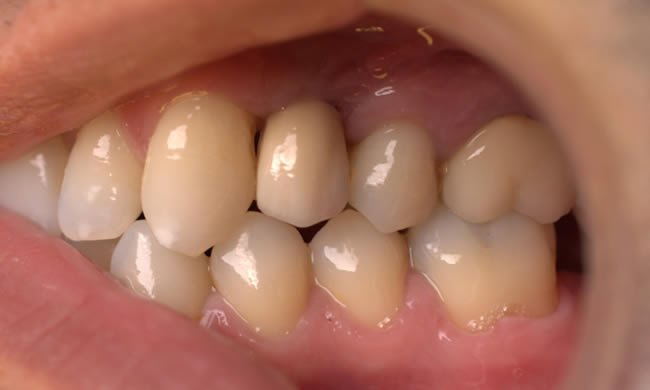

This gentleman had lost his heavily restored UL4 and decided to close the space with an implant retained crown. The thin buck-palatal width required careful placement to avoid fenestration bucally. A tooth bourn position guide was used to place the implant predictably and within the aesthetic envelope. The implant was restored after three months of osseointegration with a bonded crown.